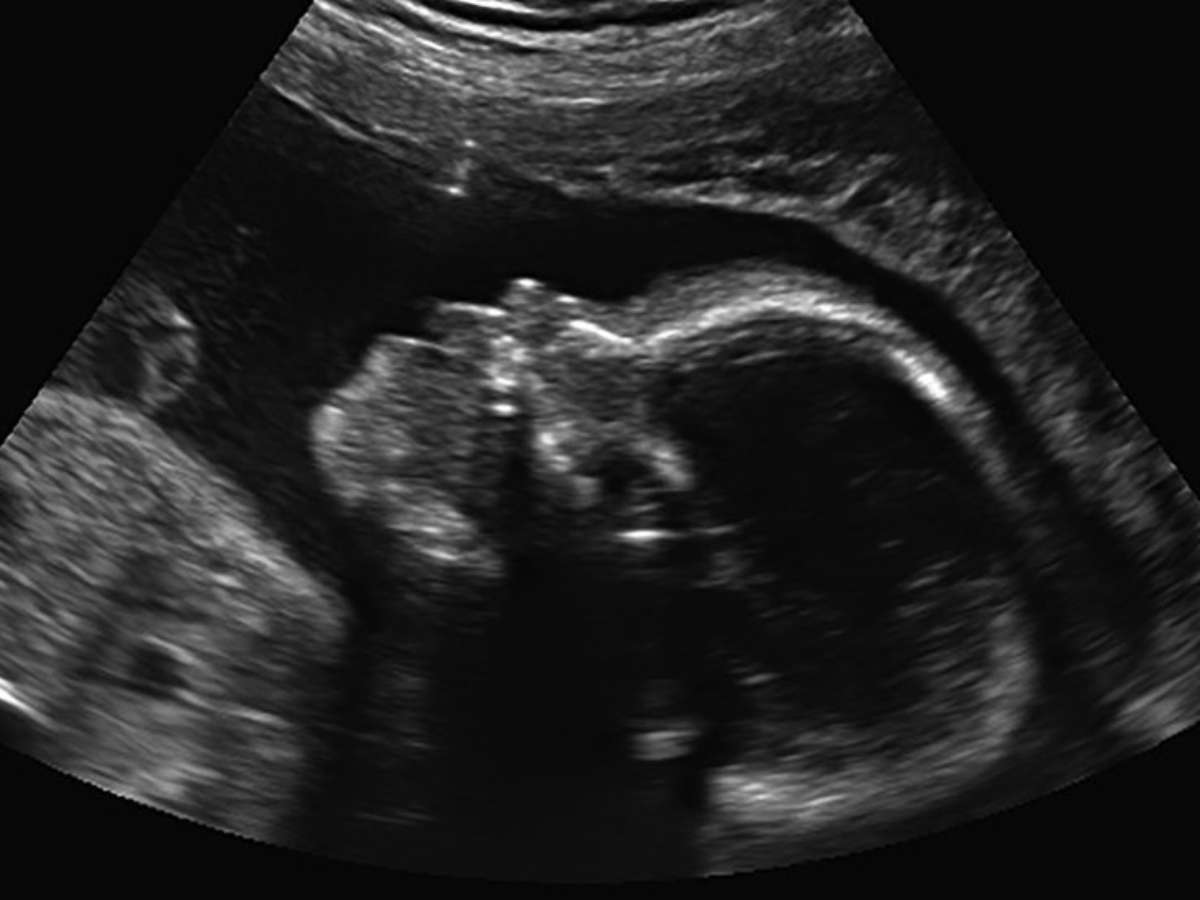

Grávida de 11 semanas, a chilena Paola Valenzuela foi com o marido e o filho, então com 9 anos, à sua primeira ultrassonografia. Uma tensão então tomou conta da sala. A equipe médica evitou dar detalhes do que acontecia, mas o menino quebrou o silêncio dizendo que não se importava com o fato de que seu irmãozinho "não tinha nariz".

Ultrassonografia

Foto: BBC News Brasil